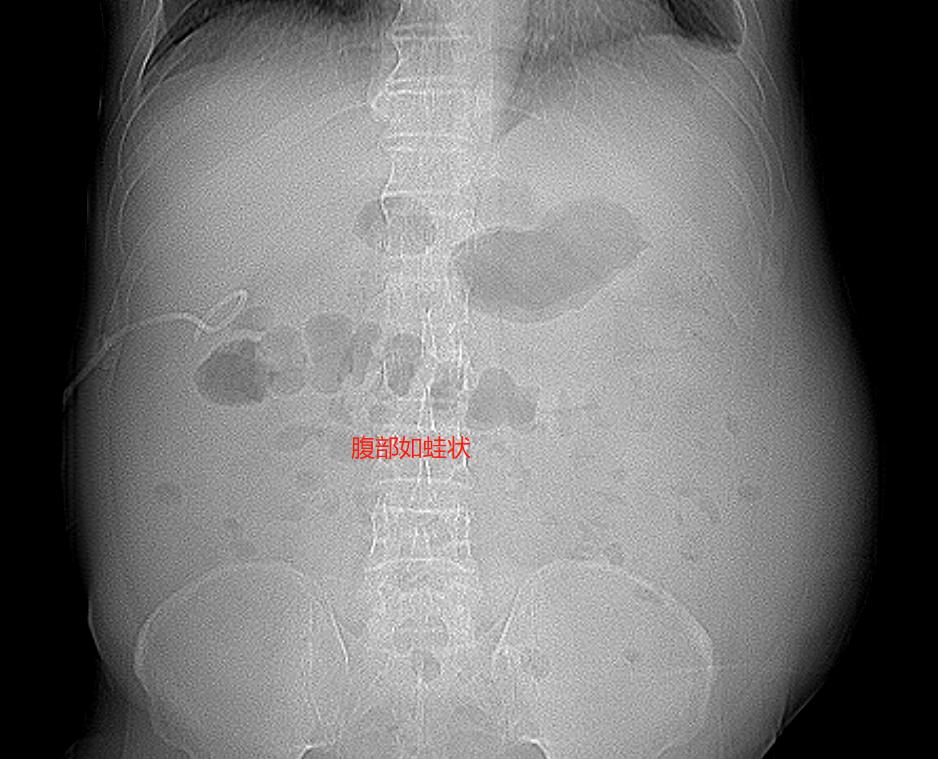

此时的他已经唇色紫褐,眼睛微突红肿布满血丝,整个腹部膨隆得像个装满水的气球,像青蛙的肚子,双下肢也是肿胀得厉害。不懂的人,看到这个样子,会以为是一个喝高了白酒的人,还是个大胖子。其实李先生并不是胖子,相比他还比较瘦小。但因为严重的肝硬化腹水,他的肚子鼓得像蛙肚,就是我们常说的“蛙状腹”。而他的面容也是比较典型的肝病面容,面色晦暗、唇色紫绀。

一检查,不得了,严重的肝硬化、大量的腹水、巨大的肝癌。往日脾气暴躁的他,知道自己的情况变得垂头丧气。